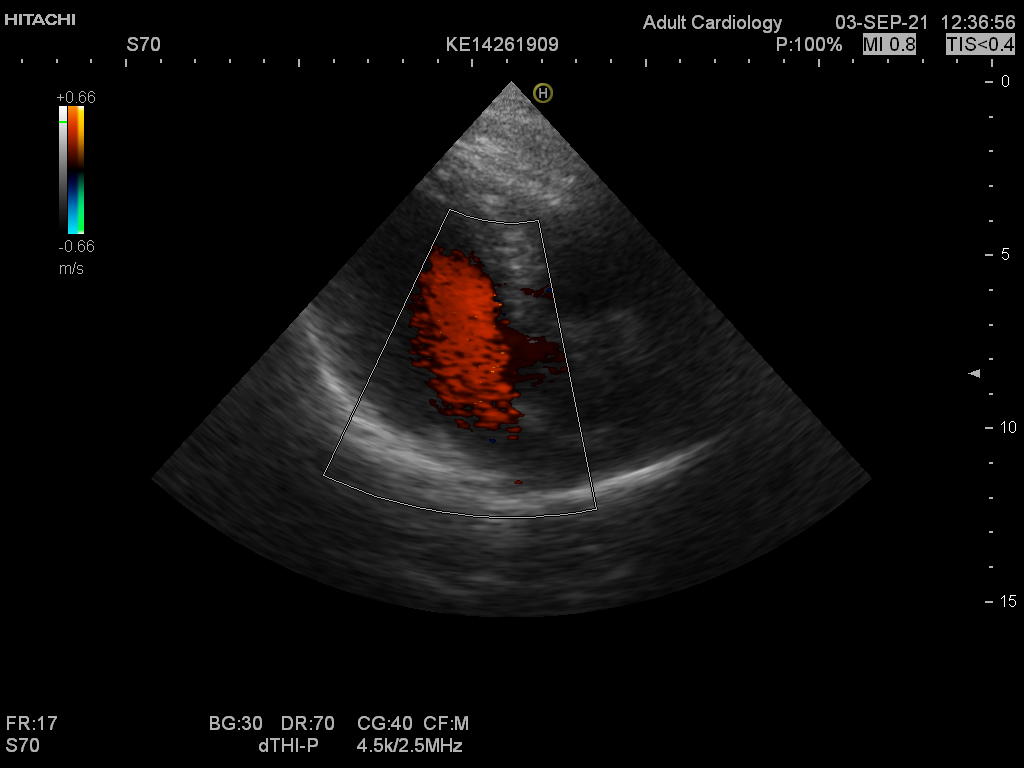

Hitachi EUP-S70 Ref Phased Array – HI VISION

Hitachi Phased Array EUP-S70 Cardio

Intended use

Cardiology and Transcranial

Hitachi EUP-S70 Phased Array – HI VISION

Hitachi EUP-S70 Phased Array – HI VISION for Cardiology and Transcranial

Compatible with Hitachi Hi Vision systems